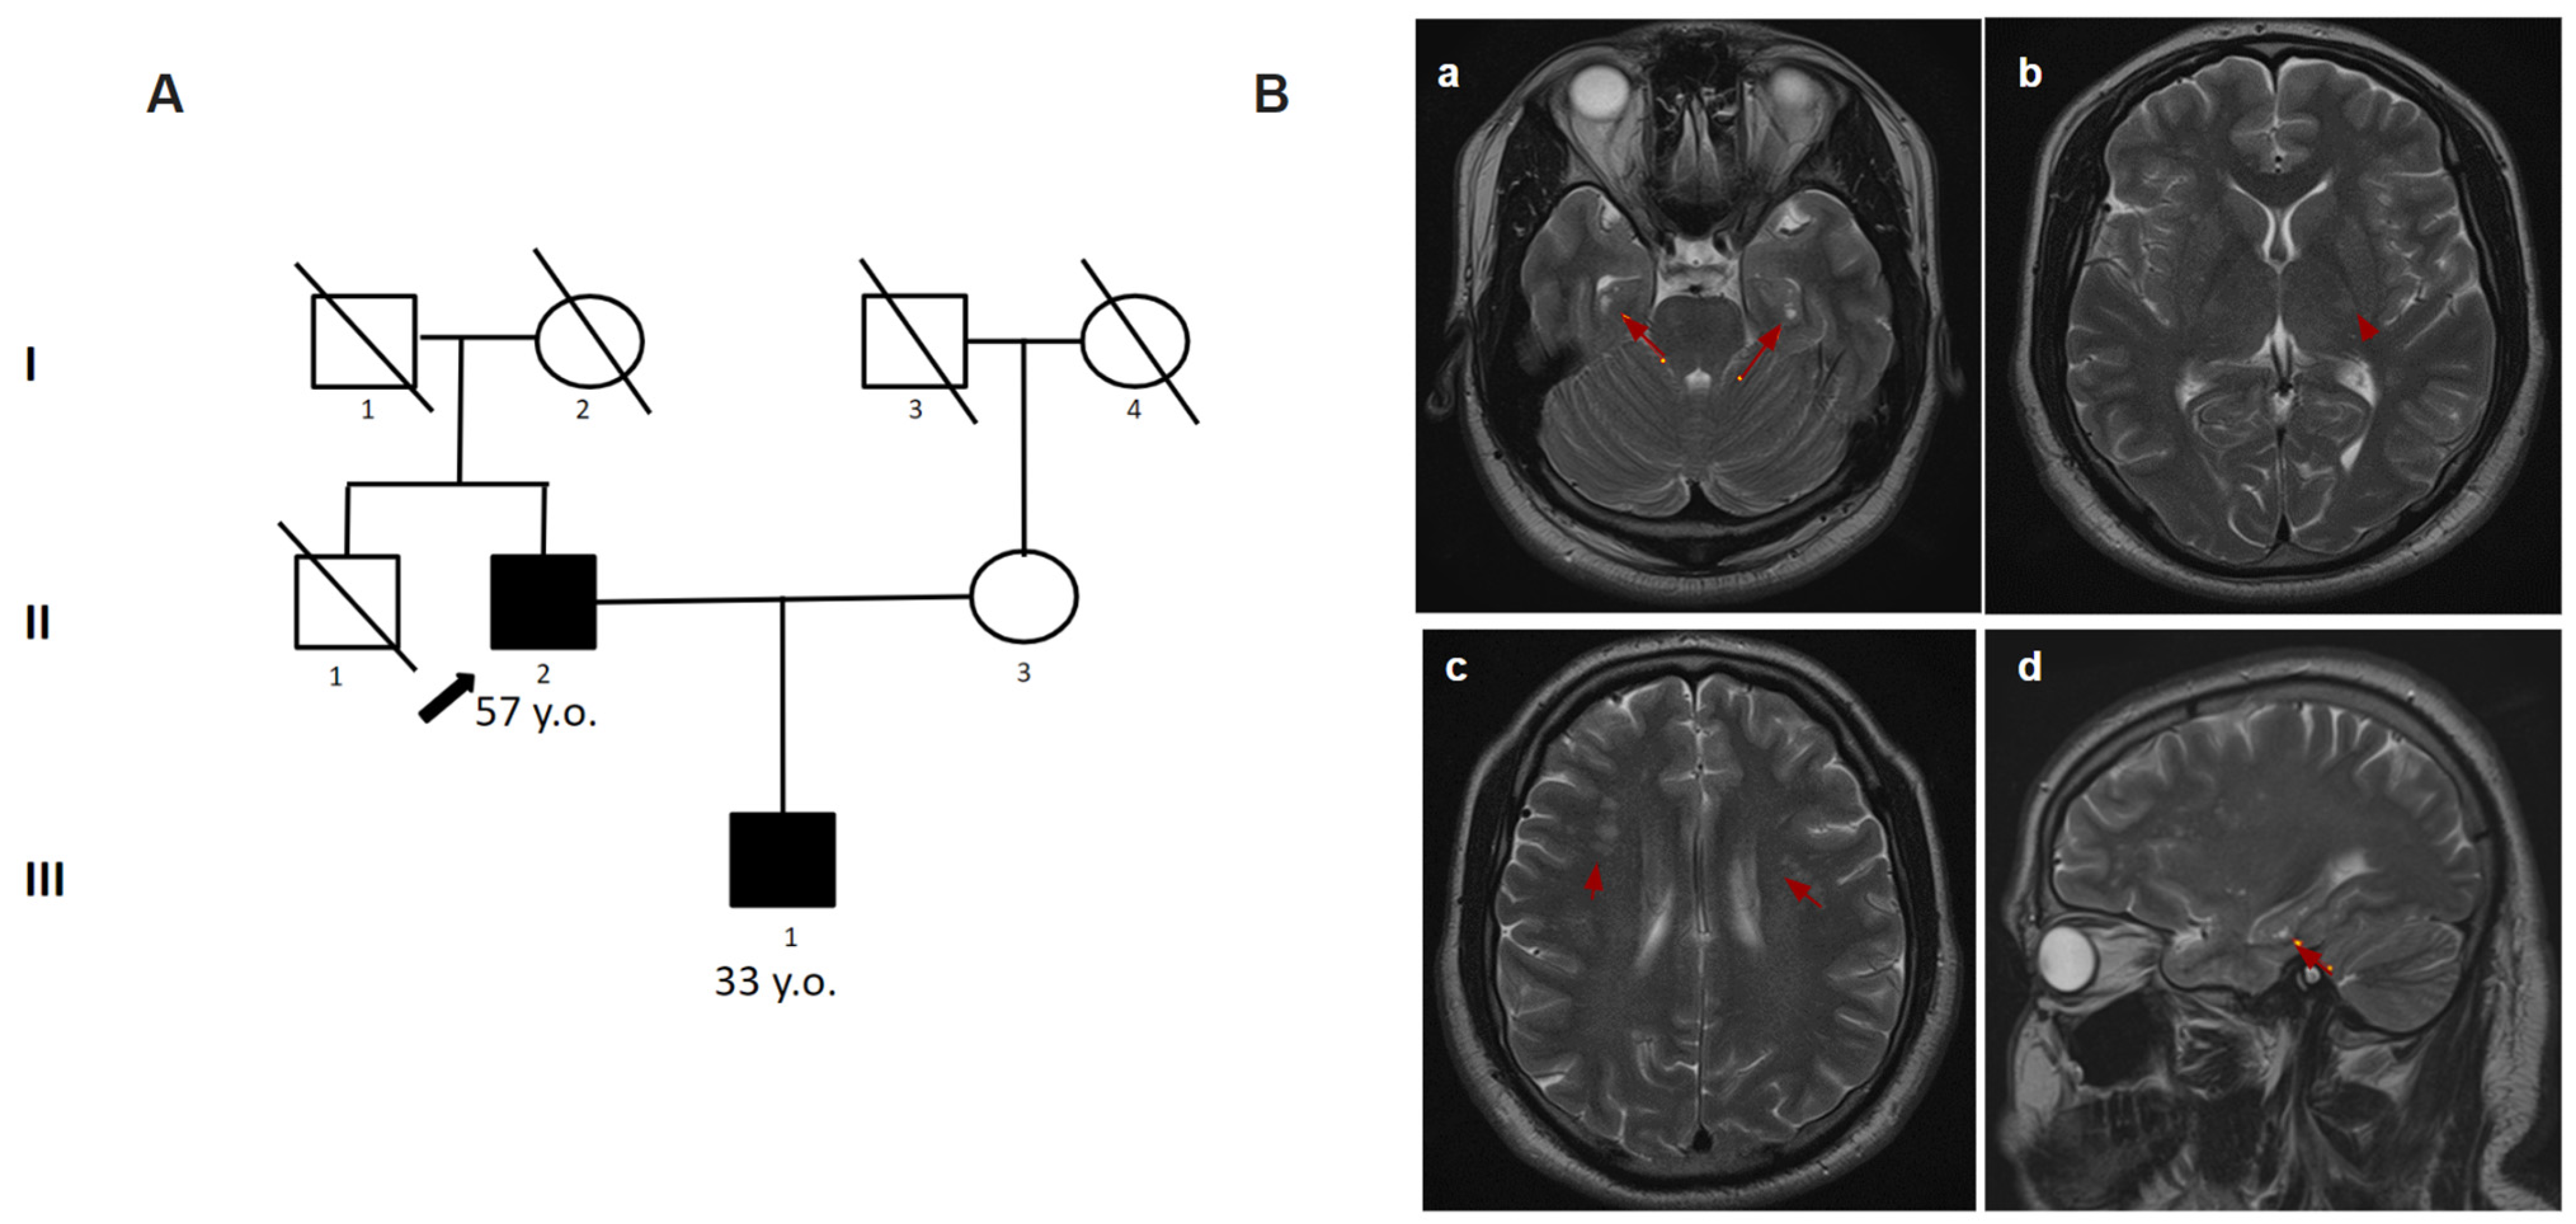

A 56-year-old man was sent to the Research Center for Medical Genetics for a consultation. He complained of memory impairment, fatigue, vision impairment, episodes of speech disturbances (while the patient himself did not realize them), unsteadiness of gait, and falling when walking downstairs. Fatigue, dizziness, speech disorders, and numbness in the left arm appeared for the first time at the age of 35. Self-relief occurred 30 min after rest. Similar attacks repeated twice within 1.5 months. According to the results of the brain MRI at the age of 48, the signs of lacunar strokes were found in the right frontal lobe, thalamus, putamen, and the pons, gliotic changes in the left hemisphere of the cerebellum, as well as multiple foci in the white matter. From the age of 47 to 56, there were approximately five episodes of disorientation, confusion, speech disorders, and dizziness. At the last hospitalization, a cerebral vascular accident (CVA) was established. In addition, at the age of 49, the patient was treated by a psychiatrist for depression and suicidal thoughts. Since the age of 56, he has not worked (as a dentist). During the examination, he showed foolishness, did not perceive his condition objectively, and did not follow the instructions (but sometimes made an effort). The speech was moderately dysarthric and reflexes were high from the hands and feet. In the complicated Romberg test, the patient was unstable. The proband’s son (Patient 4.2) complained of a periodic feeling of “heaviness” in his head, and an increase in blood pressure to 150/90 mmHg. At the age of 32, there was an attack of dizziness, disorientation, headache, and loss of speech. The attack lasted 10 min and then gradually stopped without special help. At the age of 33, two similar attacks occurred with a frequency of 1.5–2 weeks. The brain MRI showed white matter hyperintensities (Figure 4). On clinical examination, the geneticist showed no focal or neurologic symptoms. The targeted panel sequencing detected the nucleotide variant c.1547G>A (p.Cys516Tyr) in a heterozygous state in exon 10 of the NOTCH3 gene in Patient 4.1 (Table 1). By Sanger sequencing, the pathogenic variant was confirmed in his son (Patient 4.2).

Figure 4.

Pedigree and Neuroimaging features of patient 4.1 and 4.2. (A)—Pedigree of patient 4.1 and 4.2; (B)—MRI images of the brain patient 4.2 (III-1); (a–d)—multiple white matter hyperintensities (red arrows).

In the diagnosis of CADASIL, instrumental findings outperform clinical findings. Typical manifestations on MRI include WMH and lacunar infarcts. WMH is a common and early MRI feature of CADASIL. Increased signal intensity in the anterior temporal lobe has high sensitivity and specificity in most cases [15]. This change was detected in two of our patients (patients 1, 2). Signs of recurrent cerebral microbleeds (cortical–subcortical regions, white matter, thalamus, pons) are identified in most patients with CADASIL and are usually localized outside ischemic foci, which allows for considering it almost a pathognomonic sign of the disease [16]. These signs were also present in our patients (patients 1, 2, 3, 4.1). Symmetric periventricular WMH, commonly affecting the anterior temporal lobe, can be observed long before the first symptoms appear [17,18]. By the age of 35, essentially all patients with CADASIL have abnormal MRI findings, which occasionally may occur in the absence of clear clinical features [19,20]. A detailed study of the family history plays an important role in the diagnosis of CADASIL. As stated in patient 1, the key to the diagnosis was a family history. Some patients with a molecularly confirmed diagnosis may remain asymptomatic for a long time, even with well-defined lesions on brain MRI. Brain MRI may be normal early in the disease course, but by the fifth decade, significant white matter changes are the rule rather than the exception [21]. In a study of a cohort of 301 CADASIL patients, it was found that higher WMH associated with the temporal lobes and frontal gyri correlated with a milder course of the disease as compared with WMH in the pyramidal tracts [22]. However, the question of correlation between the degree of WMH changes and the severity of CADASIL patients remains open today and requires further study.